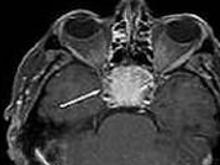

肿瘤多发生于腭弓、扁桃体、软腭缘、悬雍垂,其次见于软腭背面、下咽后壁、杓会厌襞等处。乳头状瘤外形不一,呈红色或灰白色,质较硬或软,瘤体多不大,有蒂或无蒂,单发或多发,为疣状、菜花状或颗粒状。在小儿可呈弥漫性、多发性。